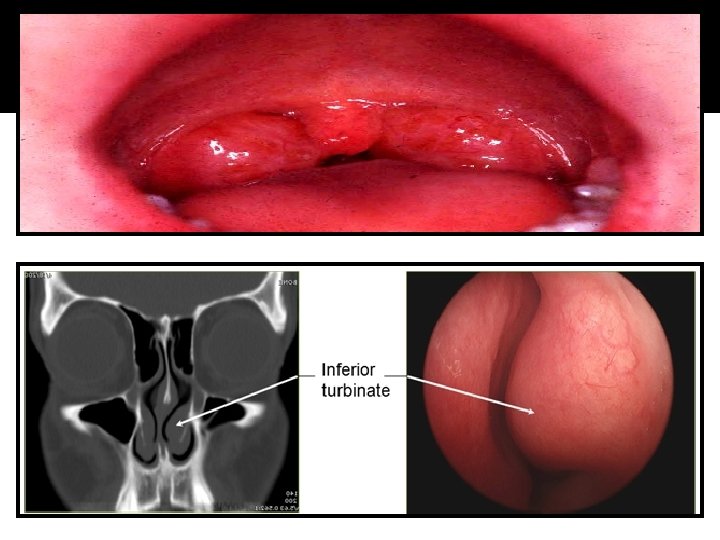

EXAMINATION OF THE RESPIRATORY SYSTEM NOSE: �The shape, size, and symmetry of the nose should be noted. In an older child, the presence of a septal deviation, polyps, injected or boggy mucosa, rhinorrhea or other discharge, and bleeding should be recorded. Nasal polyps can be associated with a variety of etiologies, including allergic rhinitis, cystic fibrosis, and aspirin sensitivity.

EXAMINATION OF THE RESPIRATORY SYSTEM �Any nasal flaring should be noted in a child with respiratory distress. Tenderness over the sinuses should be noted in patients old enough to have them. �The frontal sinuses do not start development until the middle of childhood. They are not fully pneumatized until adolescence. A horizontal crease may be seen in the skin on the surface of the nose; this signifies repetitive wiping of the nose commonly seen in allergic rhinitis (the “allergic salute”).

EXAMINATION OF THE RESPIRATORY SYSTEM �Older children (after the age of 3 -4 years) freqeuntly are compliant with this exam. The color of the oropharynx should be noted. Cobblestoning of the posterior pharyngeal wall is a sign of chronic allergic disease. The size of the tonsils and tonsilar pillars and any discharge should be noted.

EXAMINATION OF THE RESPIRATORY SYSTEM The soft plate and gingiva in newborns may • have keratin pearls. (also known as Epstein’s pearls). Any cleft palate should be noted. The uvula may be bifid, possibly indicating a submucous cleft. The number of position of teeth should be noted, as delayed or advanced dentition can be caused by some of the same conditions affecting fontanel closure.